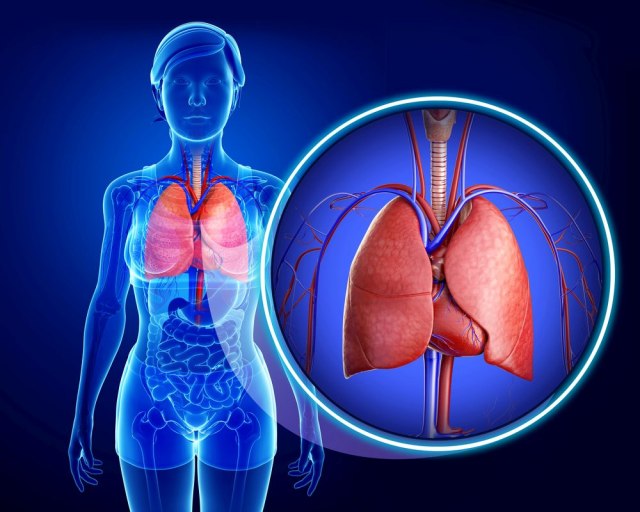

Naučno istraživanje sprovedeno u Rusiji pokazalo je da se neke vrste malignih tumora u plućima mogu uništiti upotrebom proteinskih molekula proizvedenih od nervnih ćelija.

Kiseonik je neophodan celom organizmu kako bi pravilno funkcionisao.